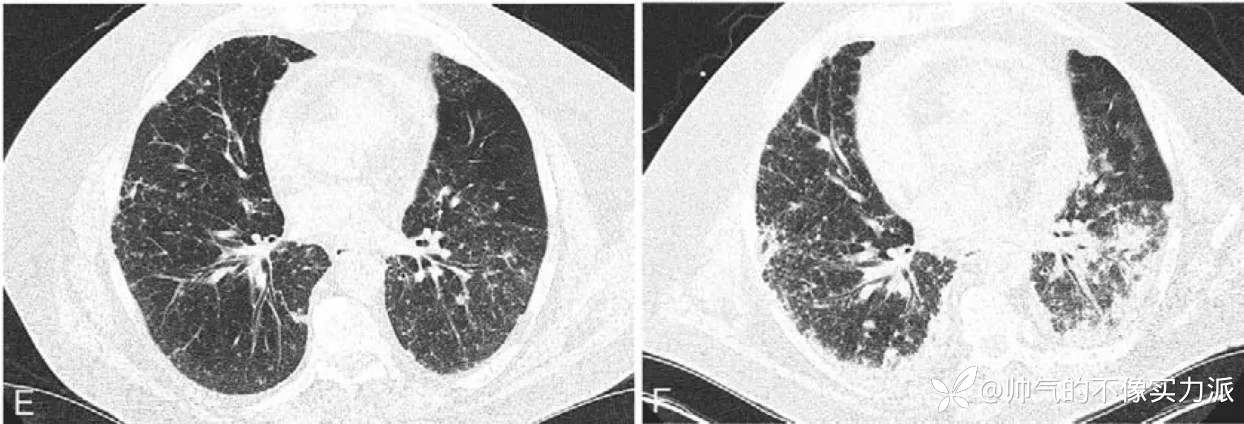

予左氧氟沙星 + 激素治疗,1 周后持续咳嗽、发热与呼吸困难加重,CT 示病灶进展,呈双侧间质性改变(图 2E)

但 4 天后病情再次进展,呼吸困难进一步加重,发热、低氧、呼吸性酸中毒及肾功能恶化。CT 示两肺渗出增加(图 2F)

图 2 初治后症状加重 CT(E);考虑结节病,激素治疗后病情进展 CT(F)

图源:参考文献 7